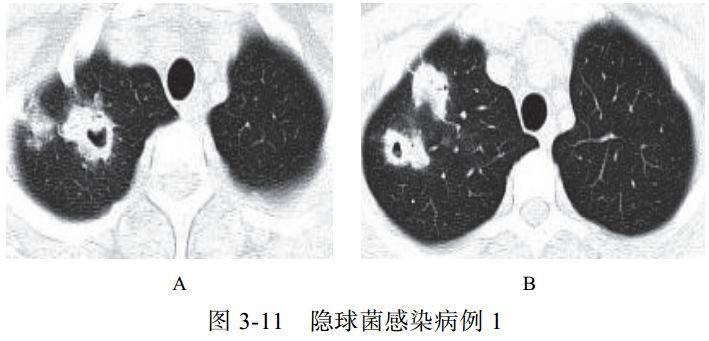

影像学表现:

(1)呈单发或多发斑片 、 类 圆形 或结 节 影, 多位 于 胸膜下(图 3-11)

(2)可出现小空洞、晕征,有时呈炎性肿块改变(图 3-12)

(3)肺门及纵隔淋巴结一般无肿大

(4)病情进展缓慢